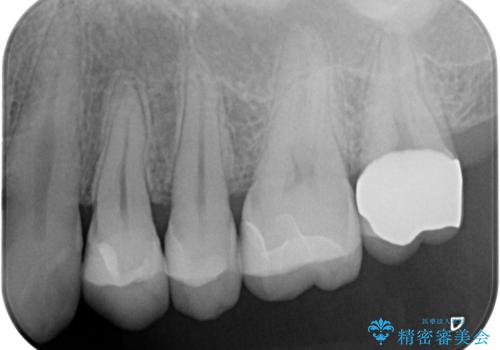

- 銀歯を無くしたいとの事で来院。

拡大鏡下でメタルを除去し虫歯がないことを確認してから白い詰め物、被せ物で治療を行いました。

- ジルコニアクラウンスタンダード・仮歯 12.1万円 e-maxインレー・7.7万円費用は治療当時の料金となります

適合の良い詰め物、被せ物が入りました。